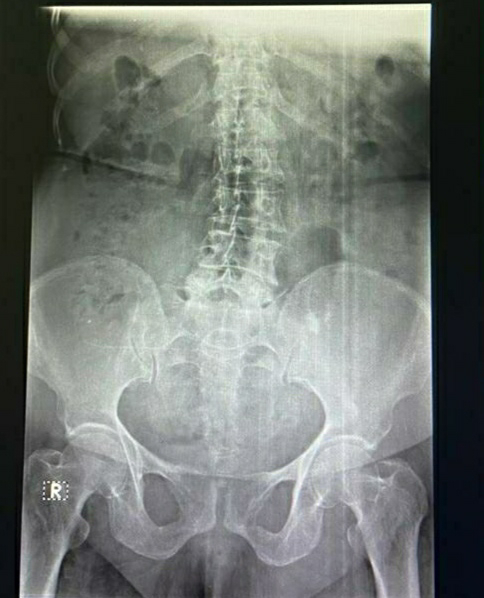

50 year old female with lumbar spondylosis

? LUMBAR SPONDYLOSIS.

DEGENERATIVE SPINE

LUMBAR SPONDYLOSIS